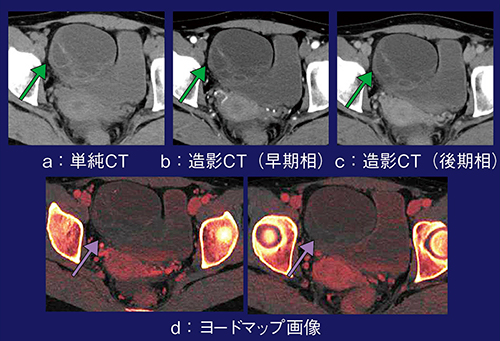

症例4は,32歳,女性,卵巣囊胞腺腫の捻転である。単純CTと造影CTの画像を比較しても,隔壁が薄いため造影されているかどうかがはっきりしないが(図4 a〜c),ヨードマップ画像では造影されていないことが確認でき,捻転と診断できた(図4 d)。本症例(捻転例)と非捻転例との比較でも,造影CTでは違いが不明確であったが,ヨードマップ画像では非捻転例は隔壁が造影され,捻転例では造影されていないことが一目瞭然であった。

また,ヨードマップ画像では,ヨード濃度の測定も可能である。ヨードマップ画像を用いて腎腫瘍と囊胞を鑑別した検討では,ヨード濃度の閾値が0.5mg/mL以上であれば,造影されているかどうかを判断できるとの報告がある2)。当院の中井らの検討でも,正常腸管のヨード濃度は2.15±0.68mg/mL,捻転腸管では0.39±0.25mg/mLであり3),やはり0.5mg/mLあたりが閾値と思われる。

図4 症例4:ヨードマップ画像による卵巣囊胞腺腫の捻転の評価